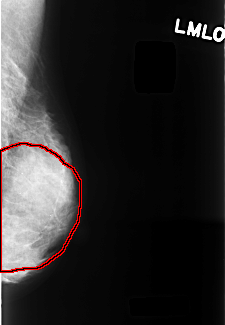

FILE: C_0329_1.LEFT_MLO.OVERLAY

TOTAL_ABNORMALITIES 1

ABNORMALITY 1

LESION_TYPE CALCIFICATION TYPE PUNCTATE DISTRIBUTION DIFFUSELY_SCATTERED

ASSESSMENT 2

SUBTLETY 4

PATHOLOGY BENIGN

TOTAL_OUTLINES 1

BOUNDARY